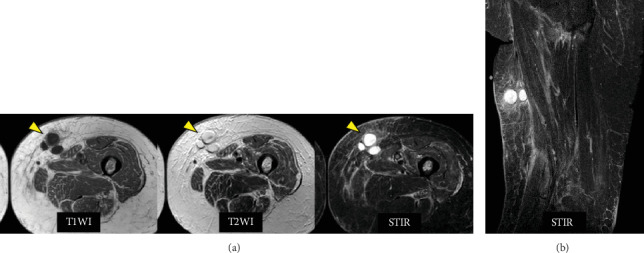

Herein, we present a rare case of periprosthetic joint infection (PJI) which was triggered by an infection with a latent subcutaneous cyst on the thigh and occurred in a strange course following total knee arthroplasty (TKA). An 87-year-old female underwent right TKA followed by left TKA 5 months later. Six weeks after left TKA, a painful subcutaneous induration appeared in the left medial thigh. Magnetic resonance imaging revealed a 30∗50-mm multifocal mass. The cystic fluid was brown and cloudy, indicating an infected cyst. Oral antimicrobial therapy was initiated for 7 days. Nine weeks after the left TKA, a left calcaneal fracture occurred. Subsequently, edema of the lower extremities and pain in the left knee gradually developed. Arthrocentesis was performed twice: joint fluid Gram staining and culture examination were negative. However, at 12.5 weeks, an alpha-defensin test of the synovial fluid was positive. Therefore, PJI was diagnosed. DAIR was performed, followed by multiantibiotic therapy. The infection subsided gradually. Edema of the lower limbs was treated with oral diuretics, lymphatic massage, and compression stockings. Consequently, the lower limb edema also improved. In this case, infection of a latent subcutaneous cyst in the thigh occurred and spread around the prosthesis due to leg edema, which was associated with loss of lower limb motion due to a calcaneal fracture. The presence of a potential thigh subcutaneous cyst is a risk factor for PJI. Moreover, lower extremity edema occurs by decreasing lower extremity motion, such as after a calcaneal fracture, and it increases the risk of extending extra-articular infection to the PJI. Potential thigh subcutaneous cysts and lower extremity edema are risk factors for the development of PJI. Orthopedic surgeons need to be aware of these facts during follow-up after TKA.

在此,我们报告一例罕见的假体周围关节感染(PJI),其由大腿上潜伏的皮下囊肿感染引发,发生在全膝关节置换术(TKA)后的奇怪过程中。87岁女性,5个月后行右侧TKA,左侧TKA。左侧TKA术后6周,左侧大腿内侧出现疼痛的皮下硬化。磁共振成像显示一个30 * 50毫米的多灶性肿块。囊性液体呈棕色浑浊,表明囊肿感染。开始口服抗菌药物治疗7天。左侧TKA术后9周,发生左侧跟骨骨折。随后,下肢水肿和左膝疼痛逐渐加重。关节穿刺2次,关节液革兰氏染色及培养检查阴性。然而,在12.5周时,滑液α -防御素测试呈阳性。因此诊断为PJI。进行DAIR,然后进行多种抗生素治疗。感染逐渐消退。下肢水肿用口服利尿剂、淋巴按摩和加压袜治疗。因此,下肢水肿也得到改善。在这个病例中,由于腿部水肿,大腿潜伏的皮下囊肿发生感染,并在假体周围扩散,这与跟骨骨折导致的下肢运动丧失有关。潜在的大腿皮下囊肿的存在是PJI的危险因素。此外,下肢水肿是由于下肢运动减少而发生的,如跟骨骨折后,这增加了关节外感染扩展到PJI的风险。潜在的大腿皮下囊肿和下肢水肿是PJI发展的危险因素。骨科医生在TKA后的随访中需要了解这些事实。